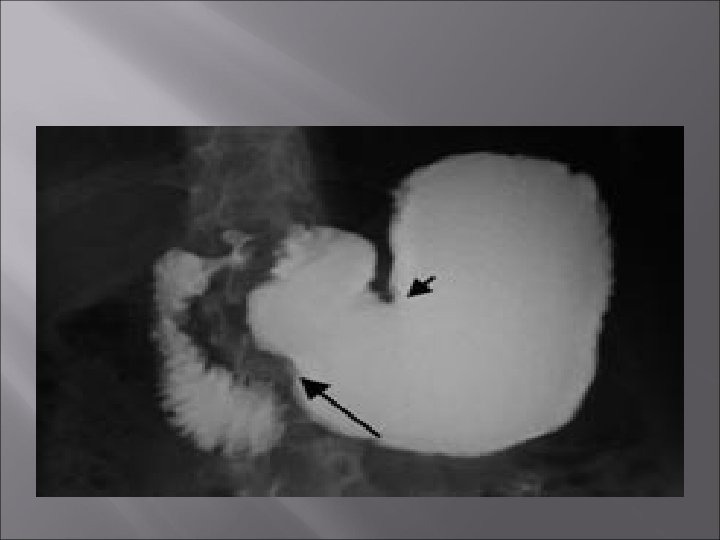

Maladie ulcéreuse gastro-duodénale Diagnostic radiologique (togd) Examens radiologiques : le profil peut montrer un ulcère en spicule ou en forme de niche avec fixité de l ’image sur plusieurs clichés, pour différencier du péristaltisme gastrique sur les clichés de profil (images d ’addition). Sur les clichés de face, ou pourra retrouver une image en cocarde. Les examens radiologiques peuvent être intéressants en cas de complications, type sténose pylorique, ou parfois en cas d ’ulcère diverticulaire.